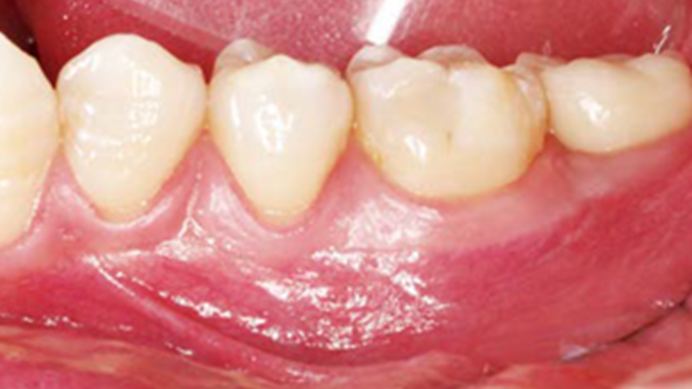

Clinical case: Bone filling into the bottom of deepest thread at 8.0mm AnyRidge fixture

- Courtesy of Dr. Kwang Bum Park -

Keywords

AnyRidge, Knifethread ,extraction socket, ,initial stability ,Allograft, ,osseointegratio ,Dr. Kwang Bum Park, , Mandibular, Single replacement, AnyRidge, Mega-oss,

Products used

Implant system-AnyRidge, Regeneration-Mega-Oss